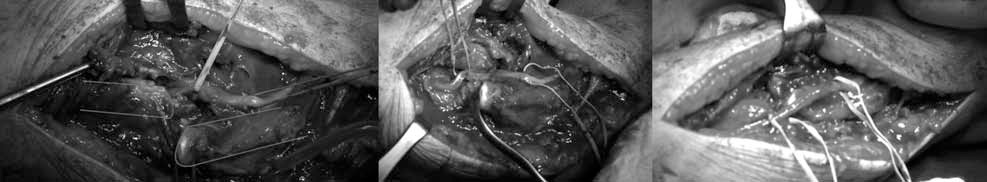

- Fig. 2. Intraoperative picture: on the left the isolation of dislocated radial nerve, neurolysis in the center and repositioning on the right picture